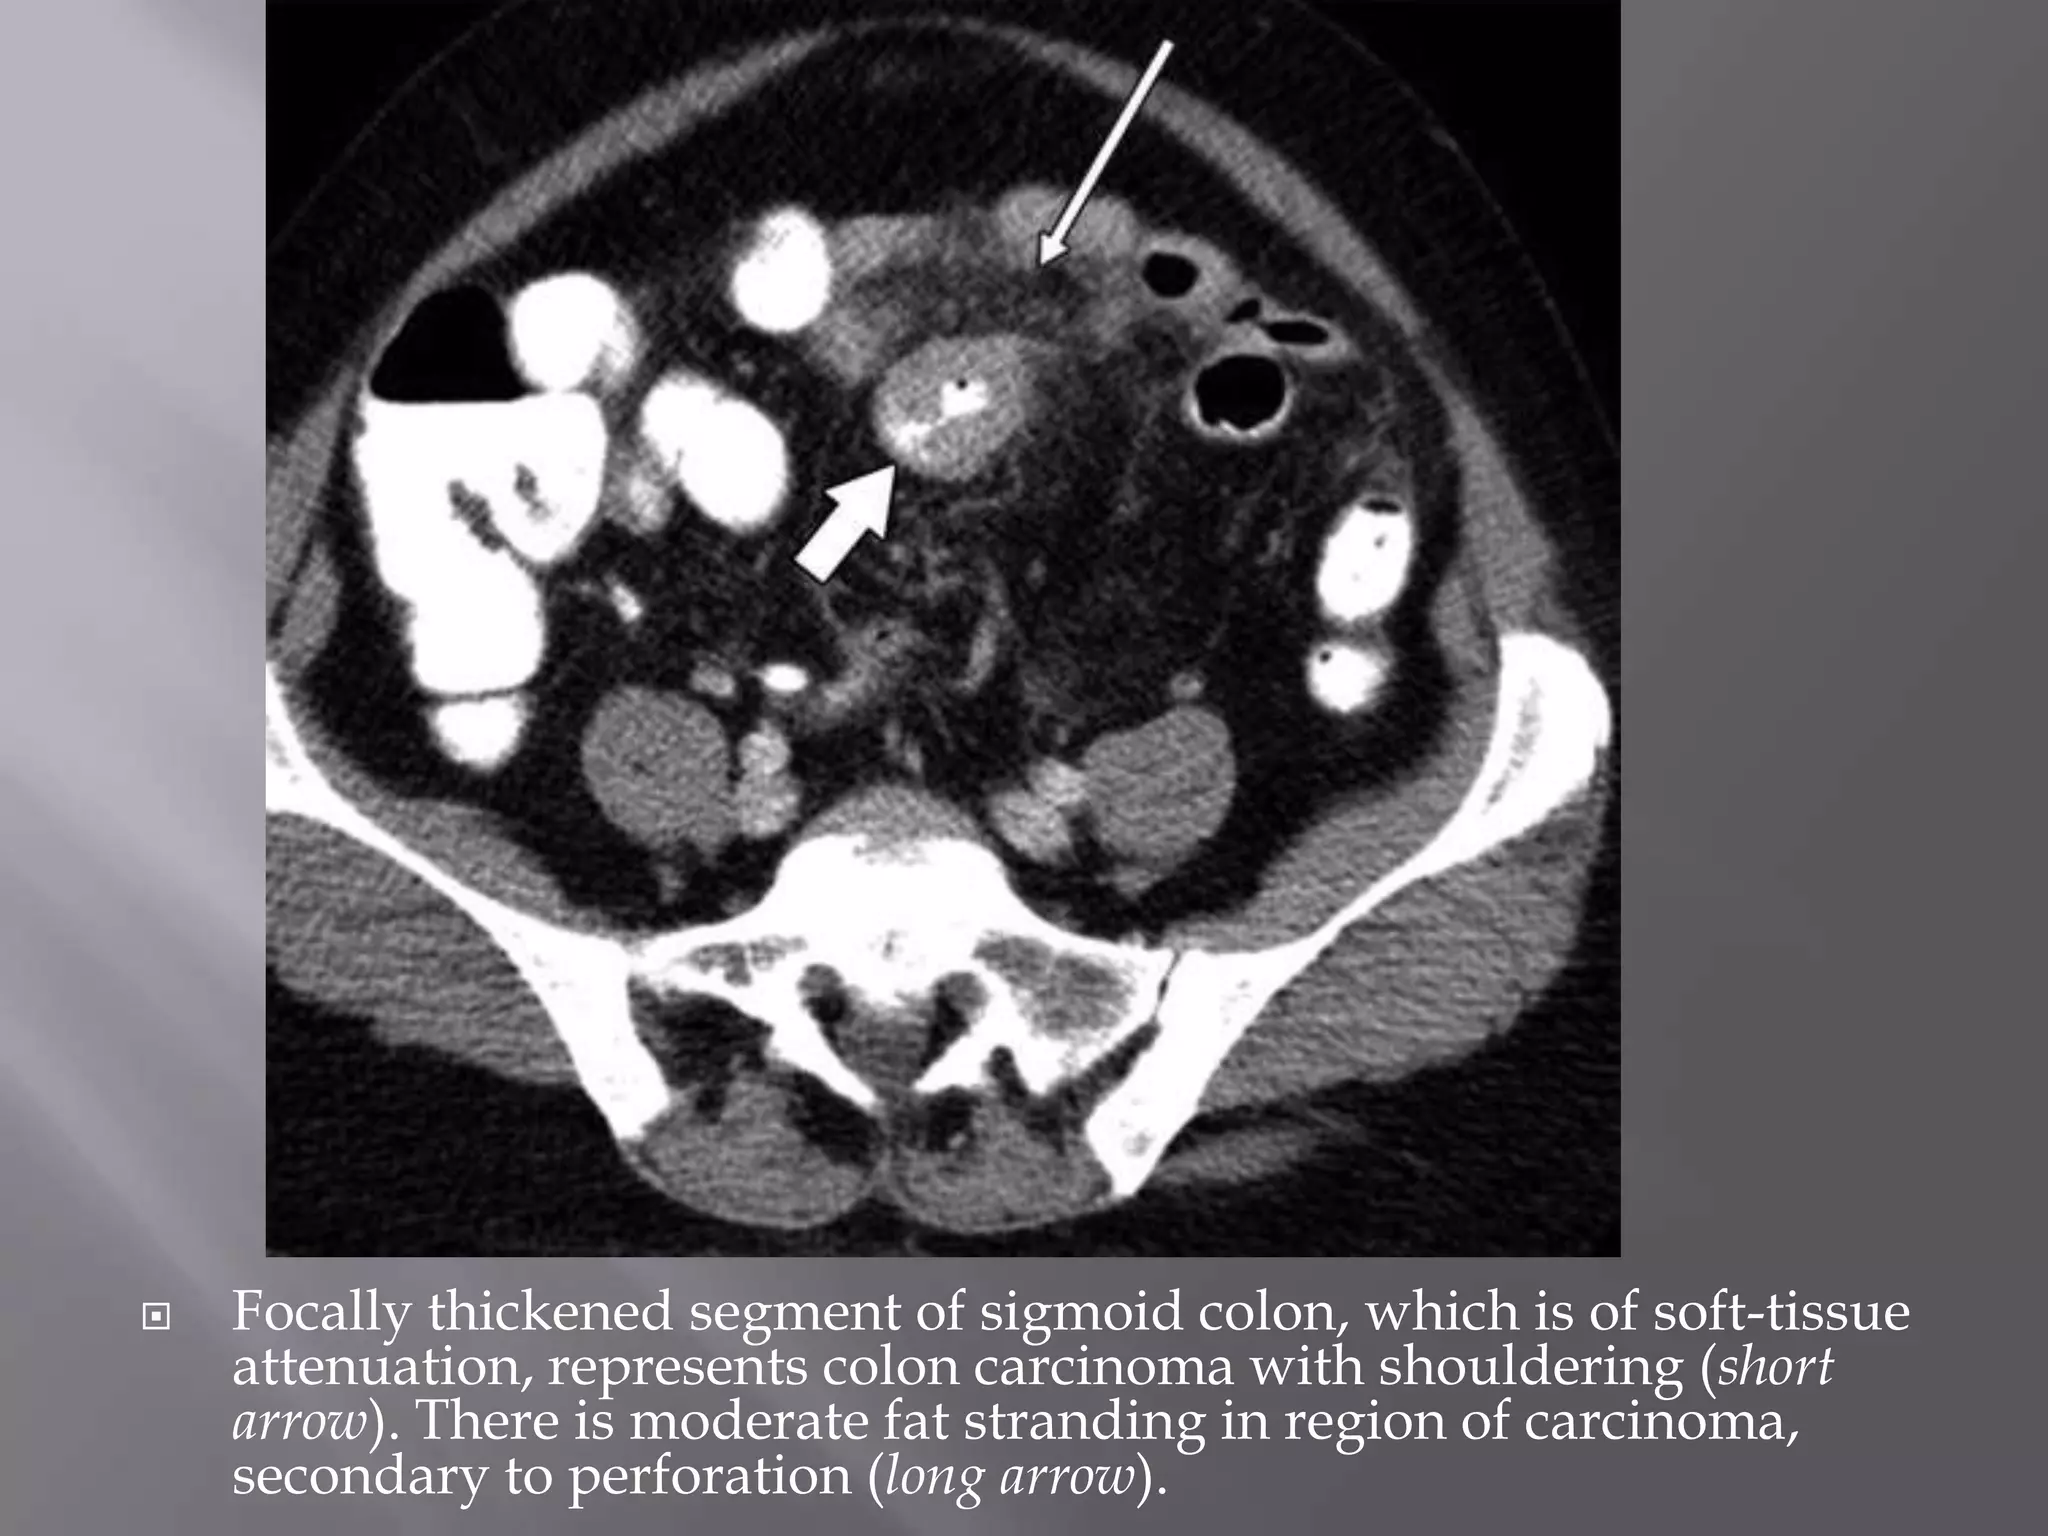

 May cause fat stranding that is difficult to

 The degree of bowel wall thickening can be a

 The bowel wall thickening is of soft-tissue

wall edema that is seen in inflammatory

 Focally thickened segment of sigmoid colon, which is of soft-tissue

attenuation, represents colon carcinoma with shouldering (short

arrow). There is moderate fat stranding in region of carcinoma,

secondary to perforation (long arrow).

 May causefat stranding that is difficult to differentiate from that seen with acute diverticulitis.  The degree of bowel wall thickening can be a helpful differential feature.  The bowel wall thickening is of soft-tissue attenuation and does not display the target sign or mural stratification signifying bowel wall edema that is seen in inflammatory processes or ischemia.

 Focally thickenedsegment of sigmoid colon, which is of soft-tissue attenuation, represents colon carcinoma with shouldering (short arrow). There is moderate fat stranding in region of carcinoma, secondary to perforation (long arrow).